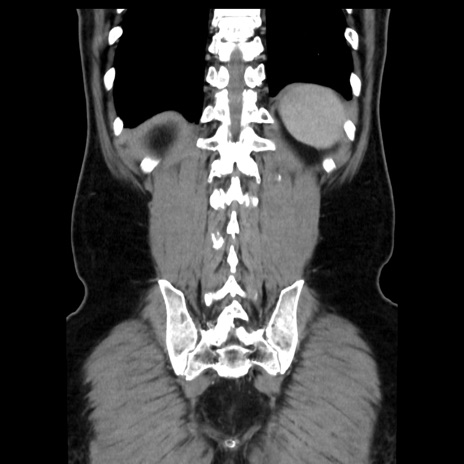

症例16(冠状断像)

【症例】 70歳代男性

【主訴】 腹痛、嘔吐

【現病歴】 約1ヶ月前より間欠的に腹痛と嘔吐あり、当院消化器内科を受診したところCTで多発する肝臓のLDAを指摘され、精査中であった。以降は消化器症状は安定していたが、2日前より嘔気と腹痛があり、同日より排便・排ガスが消失した。改善認めず、 本日、救急外来を受診した。

【既往歴】 大腸ポリープ切除後。

【身体所見】意識清明・会話良好、BT 36.3℃、BP 127/80mmHg、 P 80bpm、腹部:膨満あり、平坦・軟、上腹部正中および下腹部正中に圧痛あり、反跳痛なし、筋性防御なし。

【データ】WBC 7200、CRP 0.77